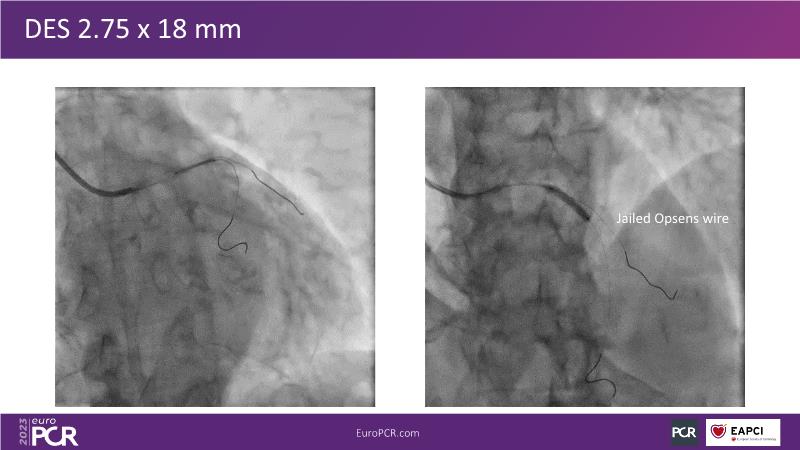

Join this session to explore the advantages of a fully optical approach in optimizing percutaneous coronary intervention (PCI) with the OptoWire III physiology wire and Nipro HF-OCT catheter. Through a practical case, you'll discover the significance of coronary physiology and intravascular imaging in bifurcation PCI and gain insights into how the performance and accuracy of the OptoWire III physiology wire can facilitate fast and reliable decision-making, particularly in side branch jailing scenarios.

- To review, through a practical case, the value of coronary physiology and intravascular imaging in bifurcation PCI

- To understand how the performance and accuracy of OptoWire III physiology wire can make the difference for fast and reliable decision-making in bifurcations, particularly through side branch jailing